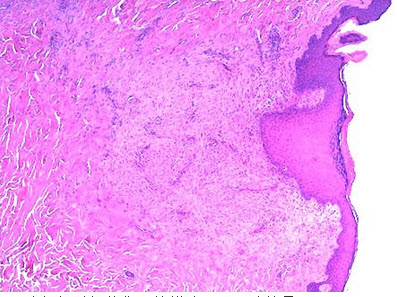

16、单项选择题

患者男性,63岁,足部溃烂3个月。于溃烂周边处区组织活检。

镜下如图所示,主要病变组成为()

A.瘢痕组织

B.肉芽组织

C.坏死组织

D.炎性渗出物

E.以上均不是

97、单项选择题

该组织镜下主要成分是()

A.纤维结缔组织

B.红染无结构物

C.新生毛细血管,纤维母细胞,炎细胞

D.厚壁小血管

E.类上皮细胞及多核巨细胞

137、单项选择题

该组织在组织损伤修复过程中的作用不包括下列哪项()

A.抗感染保护创面

B.填补创口及其他组织缺损

C.机化

D.包裹坏死、血栓及炎性渗出物及其他异物

E.增强机体抵抗力